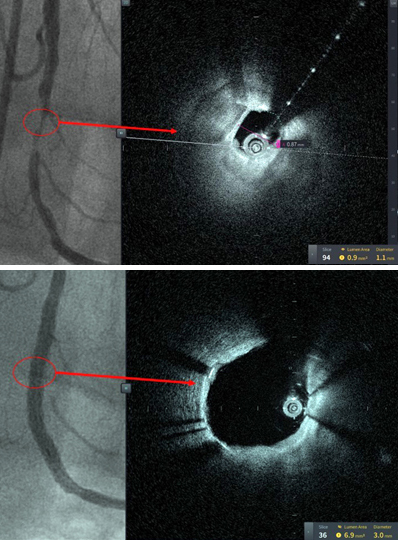

| These images are from the first patient treated with HF-OCT, performed at Tampa General Hospital, a 1007-bed academic medical center and the primary teaching hospital for the USF Health Morsani College of Medicine. Figure 1A reveals the 90% stenosis pre-intervention. Despite this high-grade stenosis, HF-OCT was able to obtain excellent image quality. Figure 1B is after coronary stenting, confirming successful stent expansion. Credit: PRNewsfoto / Tampa General Hospital. |